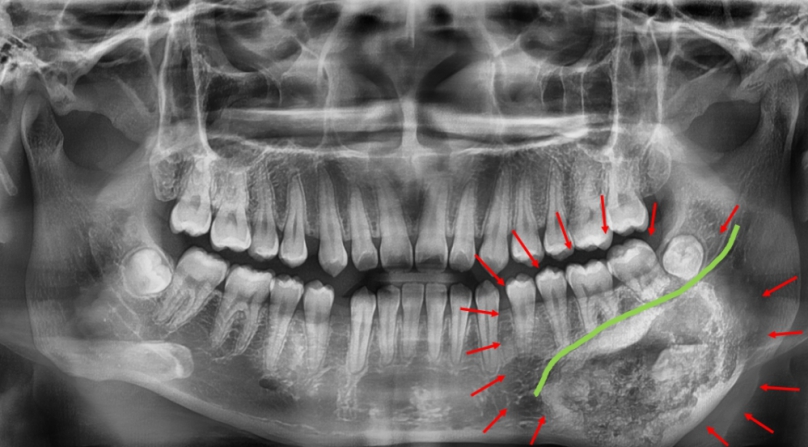

林楠瑾醫師說,「牙骨質骨化纖維瘤」邊界常與正常骨質交錯,若手術切除不夠精準,可能傷及下顎齒槽神經或造成顎骨變形,為提高手術安全和精準度,術前以「3D列印」技術製作患者顎骨立體模型,模擬腫瘤切除範圍和骨骼重建角度。

林醫師說,透過3D列印手術導引版輔助,醫師得以清楚辨識神經走向和腫瘤邊界,規劃最理想手術路徑,在完整切除腫瘤的同時,也成功保留下顎齒槽神經,維持下唇感覺和口腔功能。